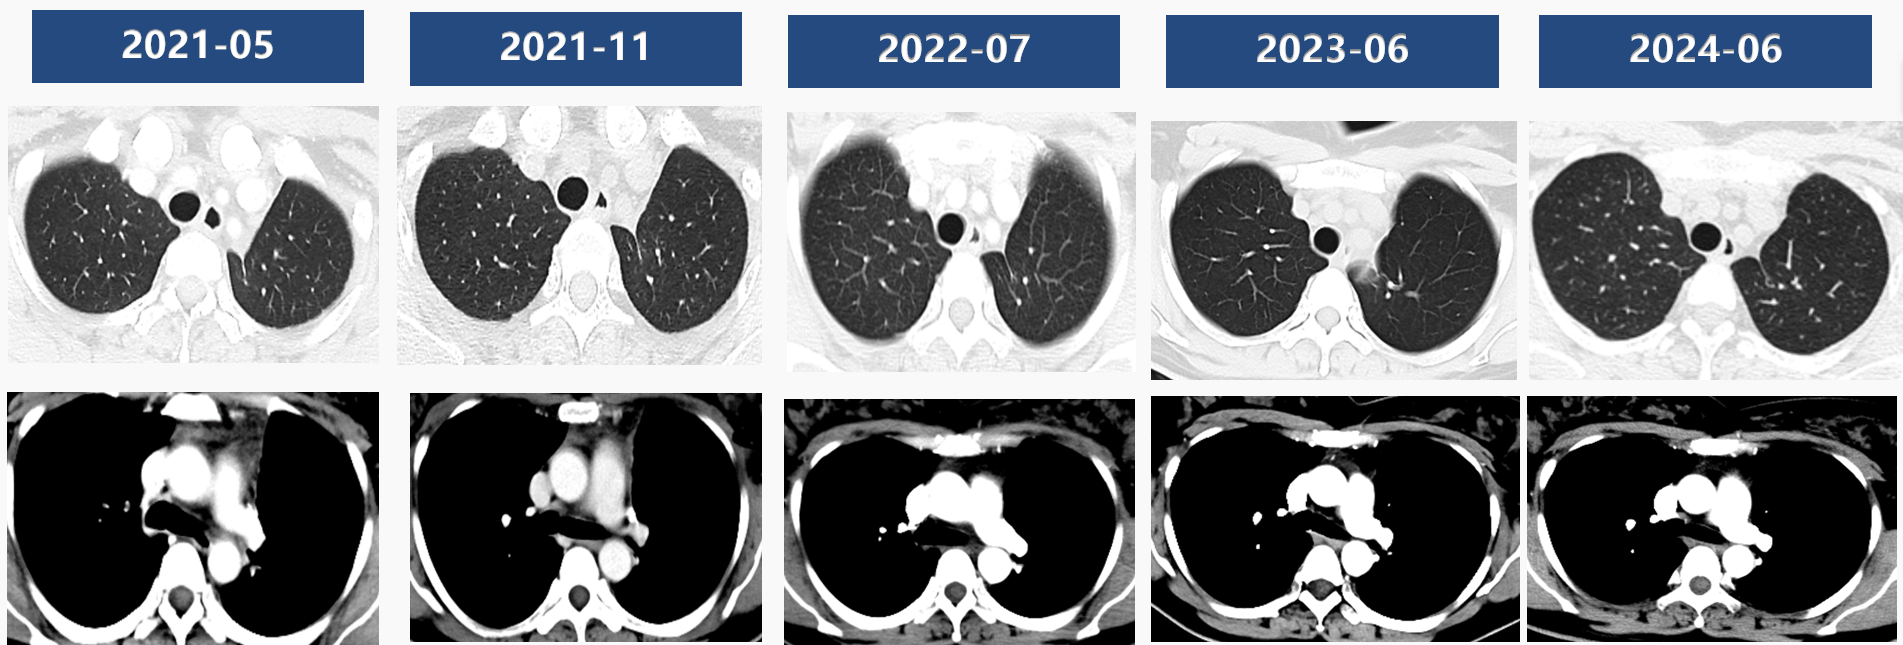

疗效评价:2程疗效评价PR,4程疗效评价PR

术后治疗:2021-05-20至2022-04-12继续行“纳武利尤单抗”单药免疫治疗,过程顺利,患者治疗中未见明显治疗相关不良反应;影像学复查未见肿瘤复发,一直保持良好的生活质量。

术后随访CT第三年: 未见肿瘤复发。

术后四年余CT复查:未见复发,目前 DFS>53个月